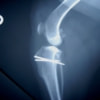

■ 症例22 ポメラニアン 1歳5か月 去勢雄

左後肢の挙上を主訴に来院した。整形学的検査、レントゲン検査より左右の膝蓋骨脱臼(左GradeⅡ〜Ⅲ、右Grade Ⅱ)を認めた。また、脛骨の前方引き出し試験の際に、引き出し兆候は認められないものの、疼痛が認められたため、前十字靭帯の損傷が疑われた。術中における、目視および関節内の操作によって、前十字靭帯の損傷や過伸展といった異常が認められなかったため、膝蓋骨脱臼の整復のみ実施した。手術手技は縫工筋及び内側広筋の解放、脛骨粗面の外側転位、滑車ブロック形造溝術、内外側関節包の縫縮を実施した。本症例は跛行もなく経過良好である。しかし、頸骨高平部の角度(TPA)が 右26.2°、左24.9°であり、解剖学的に前十字靭帯損傷のリスクが高いことから今後の経過に注意が必要である。